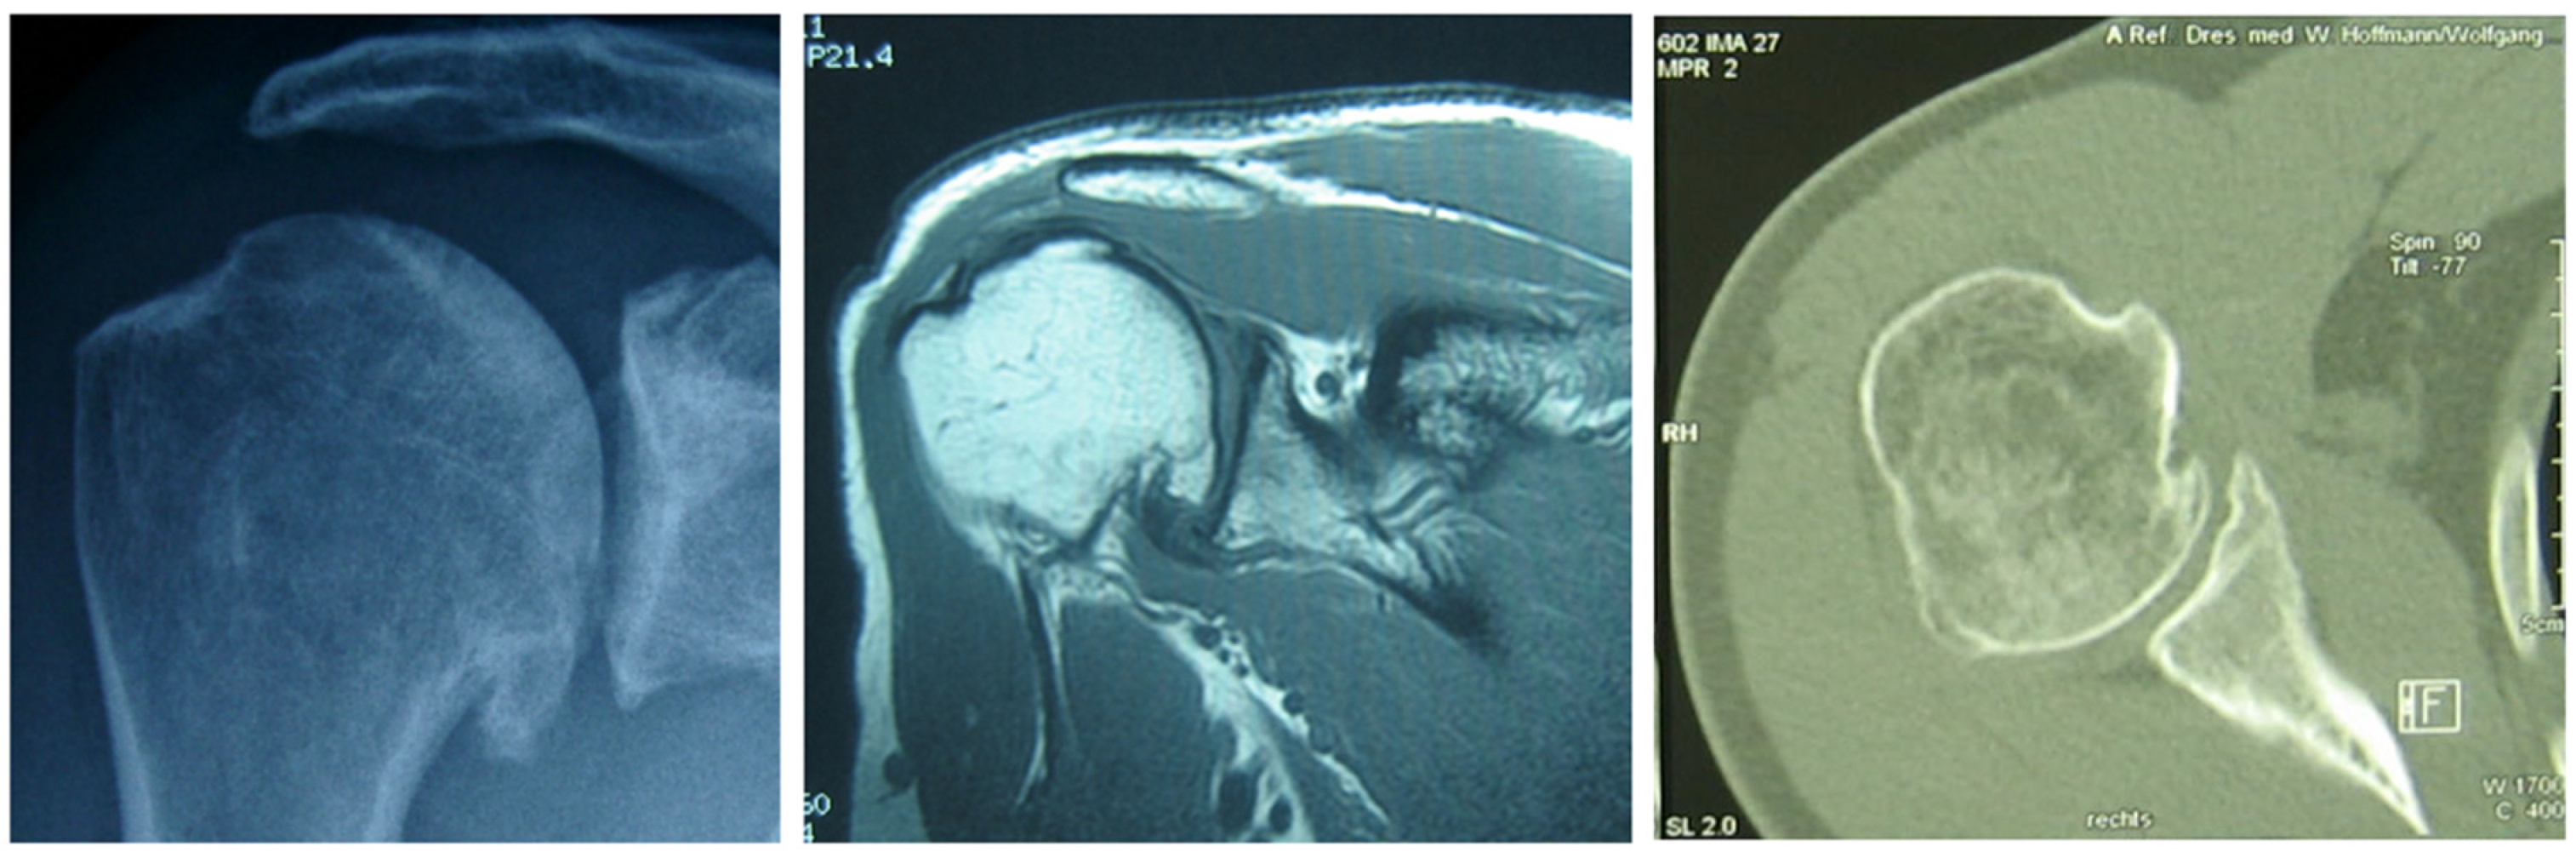

2. Physical Examinations

3. Diagnostic Radiology